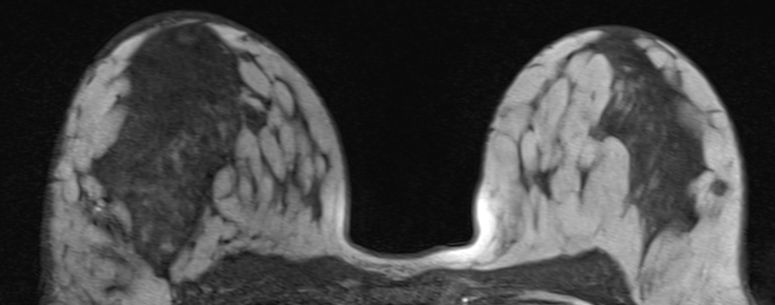

axilläre Metastasen ohne Primärtumor 51-jährige Frau mit axillärem Tastbefund. Mammographie und Sonographie o.B. Das MRT zeigt deutlich die axillären Lymphknoten.

MR im eThrive HR tra sense - Modus: Deutlich Darstellung einen 40mm großen Tumors.

Schnelle Anflutung und langsames Wash-Out sprechen für Malignität.